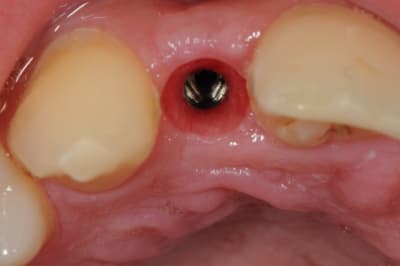

je reviens sur ce cas que j'ai un peu délaissé...

-cicatrisation

-mise en place vis de cica petit diamètre

-ensuite on augmente le diamètre en conservant et en gonflant les tissus gingivaux